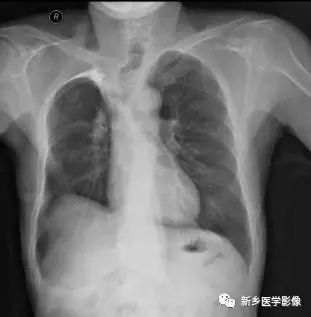

两肺间质性改变X线胸部正位片(a)、CT肺窗(b)图